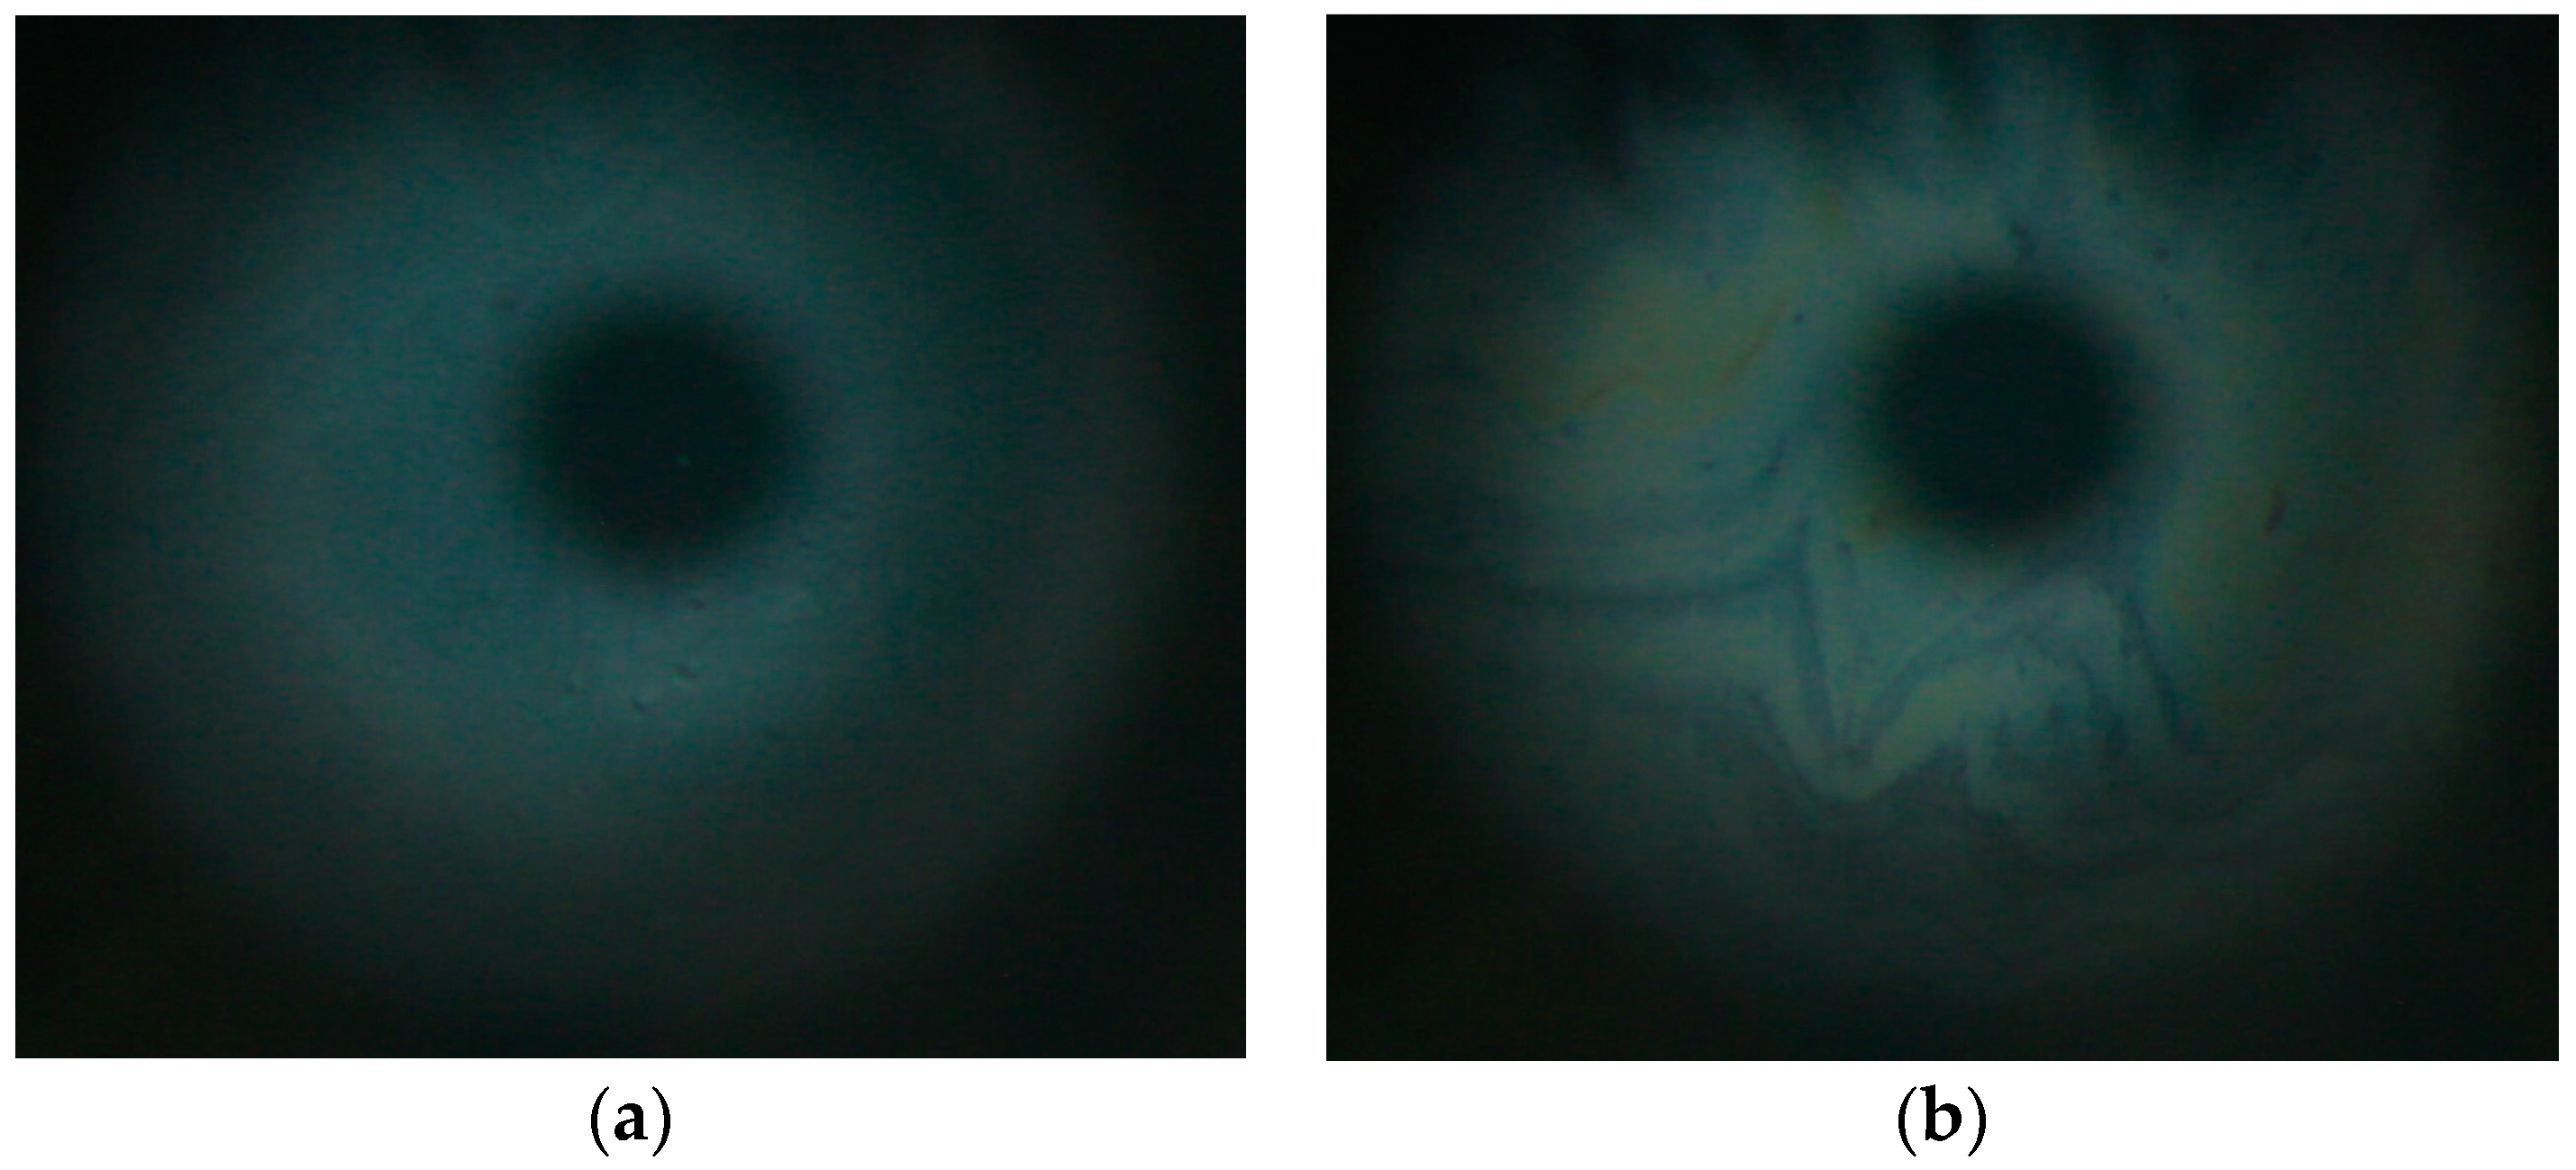

The in vitro results are in excellent agreement with in vivo specular microscopy [2] observations of the impact of RDA on the TFLLs of human volunteers. These will be discussed in detail in a separate publication, but a representative case is shown at Figure 6 (see also the videos TFLL prior RDA. mov and TFLL with RDA.mov provided as Supplementary Materials).

As can be seen, prior to instillation of RDS the tear film lipid layer has a gray color, which corresponds to 70 nm thickness, while 30 min after the instillation of RDA, grey/yellow, yellow, and blue regions appeared, which indicate an increase of TFLL thickness to the 90–120 nm range [23]. Thus, the ability of RDA oil phase to increase the overall thickness of human meibum films observed in vitro shows excellent agreement with the finding as to the capability of the nanoemulsion to thicken the TFLL in vivo at the ocular surface.

Figure 6. Typical tear film lipid layer morphology in vivo as visualized with specular microscopy (a) prior to and (b) 30 min after instillation of RDA in the tear film.